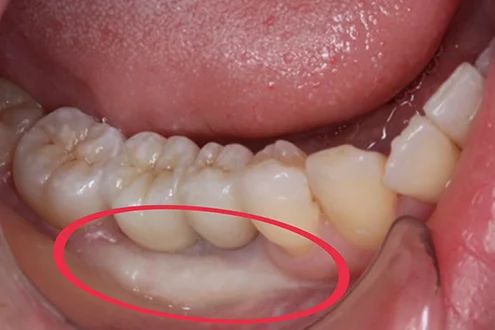

遊離歯肉移植術(FGG:Free Gingival Graft)は、歯茎が失われた部分や退縮している部分に歯肉を移植して補う治療法です。歯周病などで歯茎が退縮したときや、インプラント手術の修復のときに行われています。

- 歯周病などで歯茎が退縮してボリュームが減っている人

- 歯が長くなったと感じる人

- 抜歯後に歯茎がへこんできた人

遊離歯肉移植術(FGG)一番のメリットは、失われている歯茎の部分にボリュームを出して機能を高めるとともに、審美性も高まる点です。歯が正しく覆われることで知覚過敏や歯面の虫歯・歯周病を予防することもできるでしょう。